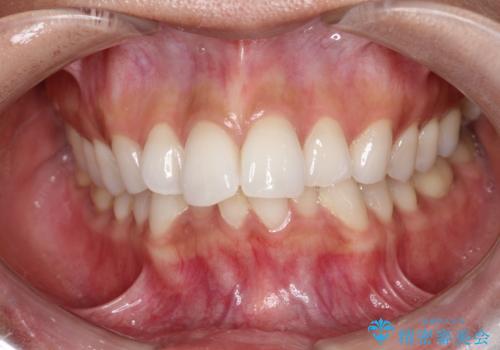

突き出た前歯を下げて理想的な横顔に。上下左右4番抜歯による審美ワイヤー矯正

担当医 河口智英